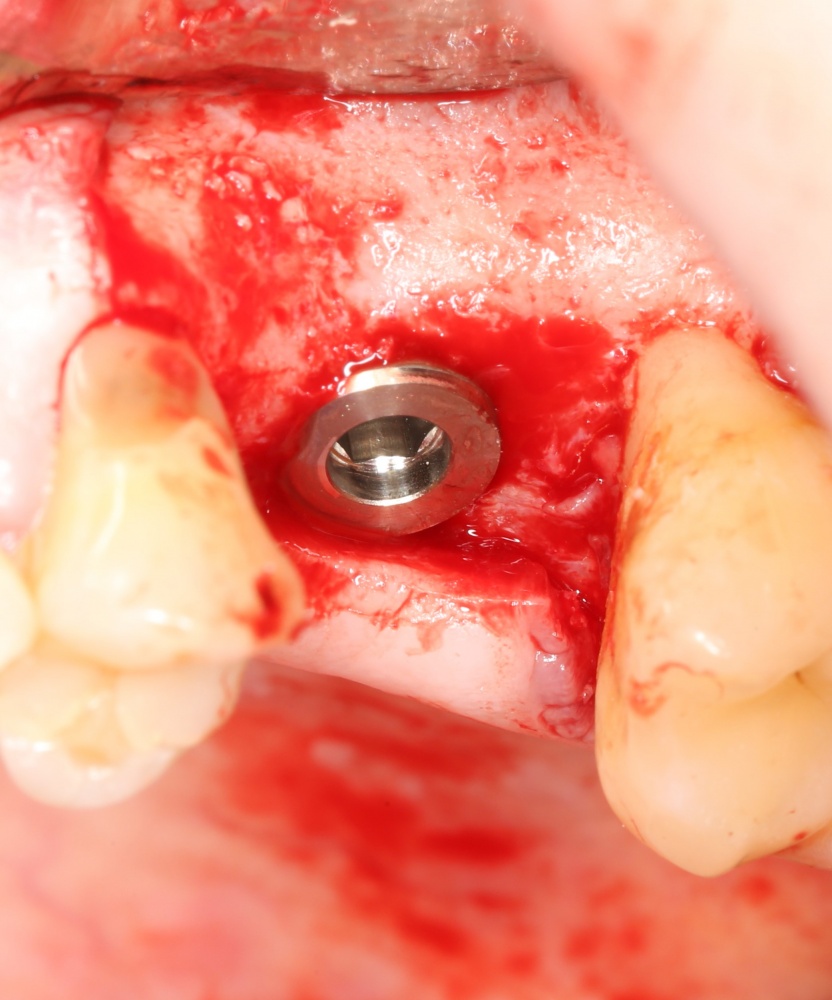

Рекомендации по установке имплантов. Для всех. Часть V.